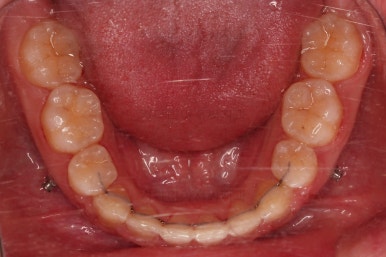

초진 시 입안의 모습이에요. 치열이 많이 나쁜 편은 아니고 앞니쪽이 조금 삐뚤어져 있네요.

특히 윗니 작은 앞니 하나가 아랫니보다 안으로 쑥 들어가 있어서 옆에 있는 송곳니가 덧니처럼 보여요.